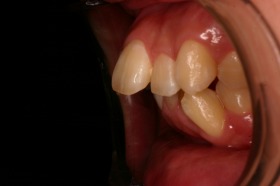

歯の矯正治療 症例ビフォー&アフター

ご覧の症例は出っ歯を矯正治療でキレイにしたケースです。

ご覧の矯正歯科治療の場合は、抜いて矯正歯科

治療していますが東京世田谷矯正歯科センターでは

非抜歯矯正歯科治療をベースにしています。

どうしても抜かないとキレイにならない場合のみ

抜歯して矯正歯科治療しています。